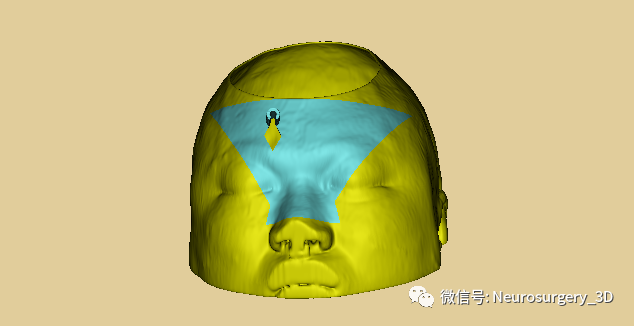

1、利用Ruler测量出穿刺血肿靶点至穿刺外口的距离,并设计出穿刺路径顺血肿长轴走形在血肿中心(并非如下图所示所有穿刺路径均与矢状面平行、请注意穿刺深度),避开颅内重要结构如额窦、上矢状窦等。

入颅点避开了额窦、上矢状窦

透视化血肿状态下显示穿刺路径走形在血肿中心

4、生成穿刺导板面具